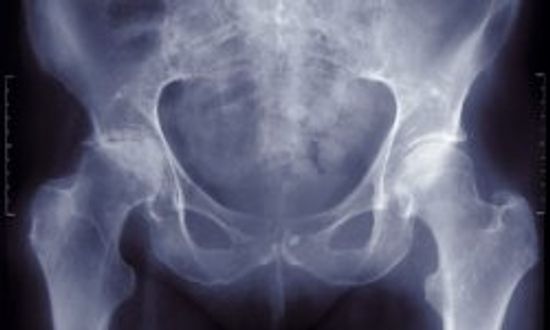

骨质疏松症诊断和风险因素

骨质疏松症的问题和答案

骨质疏松症的治疗